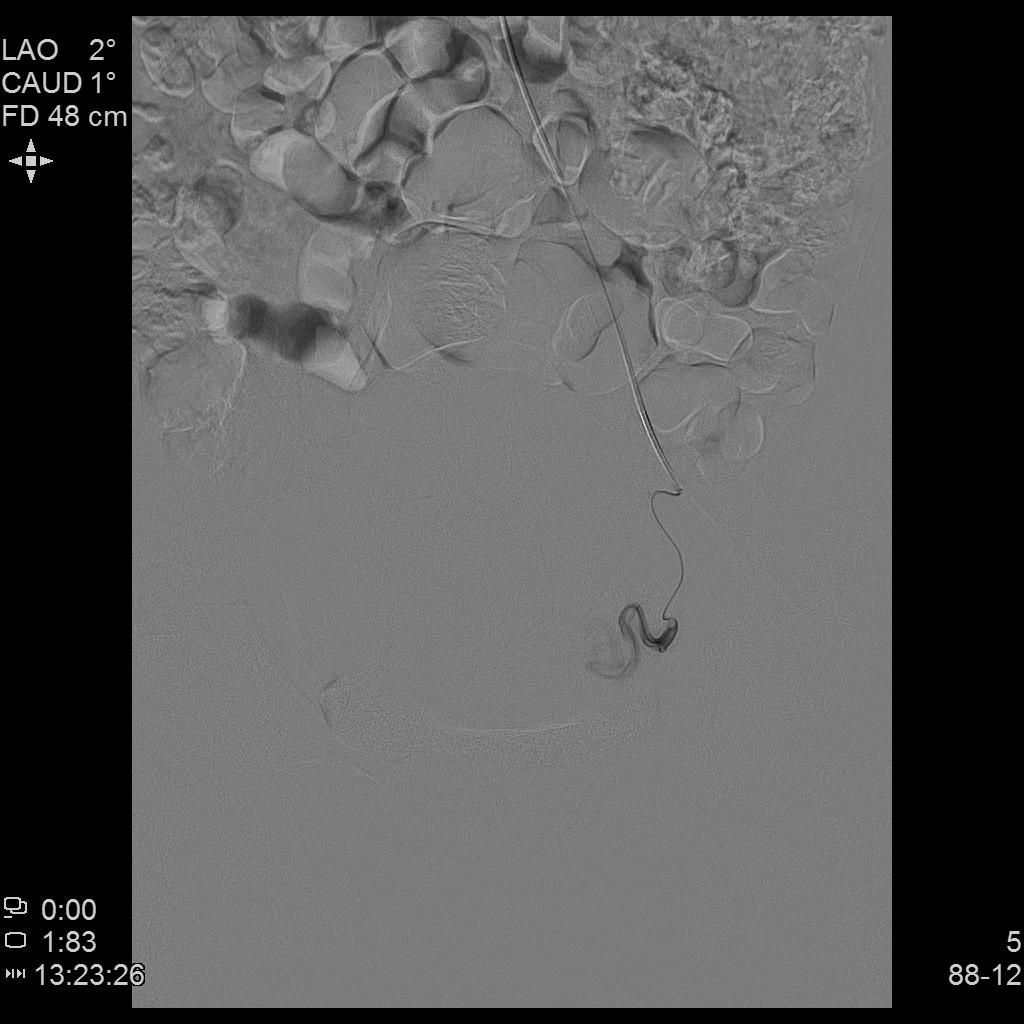

- 插管至右侧子宫动脉,显示子宫右侧病灶情况

右侧子宫动脉造影

左侧子宫动脉造影